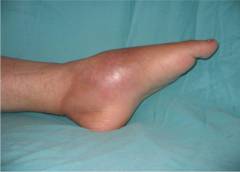

Локальный остеомиелит проявляется сильной болью и отеком, с повышением температуры. Прорыв гноя в межмышечное пространство уменьшает боль.

Клинический местный остеомиелит проявляется интенсивной распирающей болью, охватывающей пораженную кость. При осторожной перкуссии можно выявить область наибольшей болезненности над воспалительным очагом. Нагрузка на кость и движения в соседних суставах ограничены из-за болевых ощущений. Кожа над воспаленной зоной горячая и красная. Яркий отек, особенно при межмышечной флегмоне, вызывает натяжение кожи и блеск. При пальпации над флегмоной может ощущаться флюктуация. Температура тела колеблется от 37,5 до 38,5 градусов. Прорыв гноя через надкостницу в межмышечное пространство облегчает боль. Образование свища приводит к исчезновению болевых ощущений и других признаков воспаления.